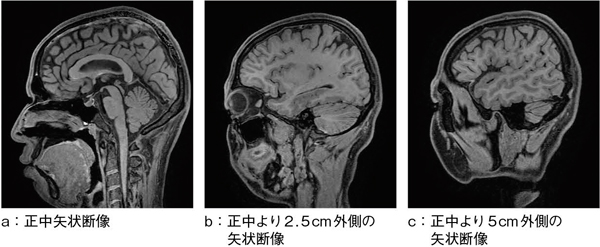

1mm isotropic dataは,readout,位相,スライス方向にzero fill interpolationより補間され,見かけ上0.5mmの空間分解能を持っている(図1)。そのため,拡大処理をした下垂体部の描出も良好で(図2),下垂体後葉がしっかり高信号となり,コントラストも良好である(図2↑)。図2 bの冠状断像では,大脳基底核だけでなく,視交叉周囲の脳脊髄液と中大脳動脈のflow voidのコントラストもしっかりと保たれている。

図1 isoFSE T1強調画像

図2 isoFSE T1強調画像(下垂体部の拡大)